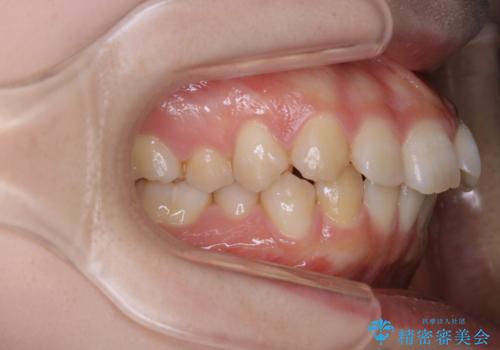

前歯の重なりは奥歯のズレが原因:まとめてインビザラインで治す

- 前歯の重なりが気になるとご相談にいらした方です。前歯のがたつきは奥歯の噛み合わせのズレが原因となっていたため、インビザラインFULLにて奥歯からしっかり治療していきました。

前歯のがたつきだけを治そうとした場合、噛み合わせは二の次なってしまう事が多く、せっかく綺麗になった歯並びも後戻りしやすくなります。

見た目だけでなく奥歯を移動させて噛み合わせの改善までが行えるのはインビザラインであるからこそです。奥歯の噛み合わせからしっかり機能させることで、長期間にわたって綺麗な歯並びを保ちやすくなります。